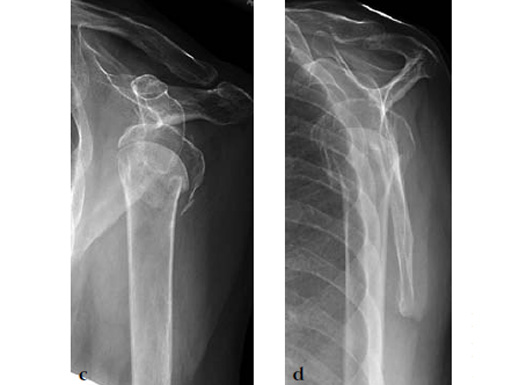

A 72-year-old woman suffered a four-part fracture of the left proximal humerus following a fall from a standing height. The patient underwent open reduction and internal fixation of the proximal humeral fracture.